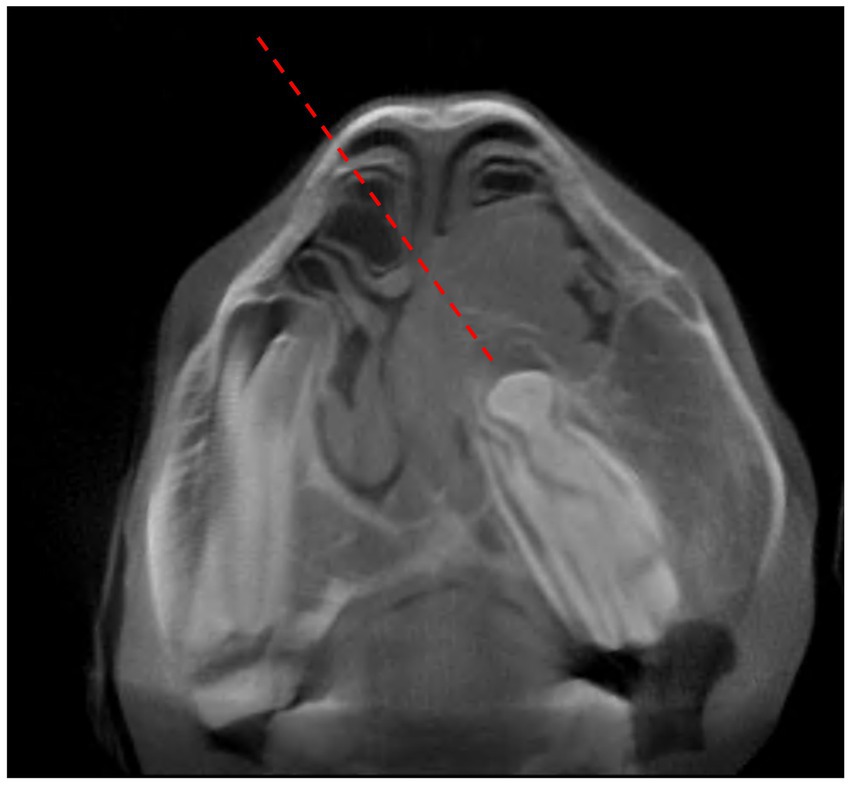

For cases 14 and 15, a conchofrontal or rostral maxillary approach, respectively, was made for CAS repulsion. After locating the ideal site for creating the approach with the navigated pointer, a skin incision to the surface of the bone was performed, followed by wound retraction with Gelpi retractors before a 25 mm manual Galt trephine was used to fenestrate the bone and gain a direct approach to the apical region of the affected maxillary cheek tooth. Subsequently, the targeted maxillary cheek tooth or tooth fragments were repulsed with a navigated 8 mm cylindrical dental punch under real-time orientation and depth control. In case 16, an osteotomy was performed in the contralateral right nasal bone to gain access through the right dorsal nasal concha to the displaced obliquely orientated cheek tooth 208 (Figure 7). Navigated cylindrical dental punches of different diameters were used to complete exodontia.

Figure 7. Transverse preoperative cone beam computed tomographic image through tooth 208 (case 16). Note the obliquely orientated and displaced cheek tooth with its tooth roots obstructing the left nasal passage. There is a periapical space occupying mass causing deformation of the left ventral and dorsal conchae. The dashed line represents the direction of repulsion through the right dorsal concha.